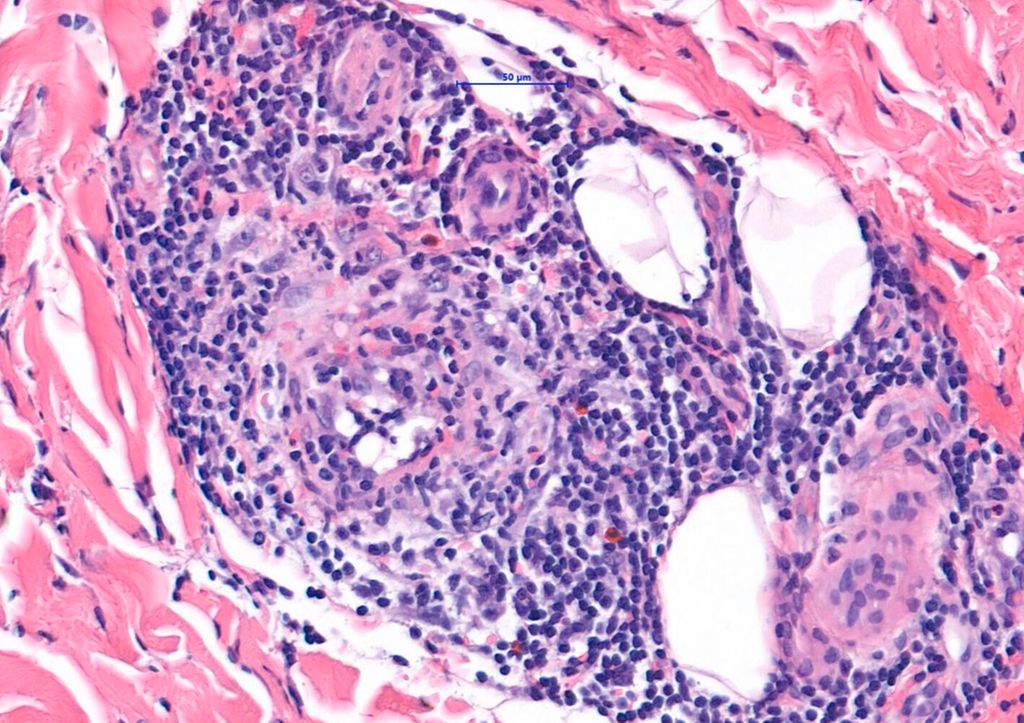

Abb. 2: Histologie: dichte Infiltrate aus Immunzellen, Fibrose und Lipidablagerungen im Bindegewebe

Bei der EED handelt es sich um eine chronische leukozytoklastische Vaskulitis. Histologisch zeigen sich in frühen Stadien eine dichte neutrophile Infiltration mit Fibrinoidnekrosen der Gefäßwände und extravasale Erythrozyten, was einer leukozytoklastischen Vaskulitis entspricht. In fortgeschrittenen Stadien dominieren dichte Infiltrate aus Lymphozyten, Histiozyten, Eosinophilen und Neutrophilen. Außerdem kommt es zu Dermalverdickung, Fibrose und Lipidablagerungen im Bindegewebe (Abb. 2). Die Epidermis zeigt sich unbeteiligt.